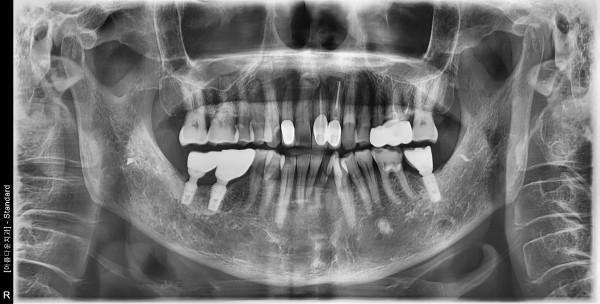

60대 남성 임플란트 식립